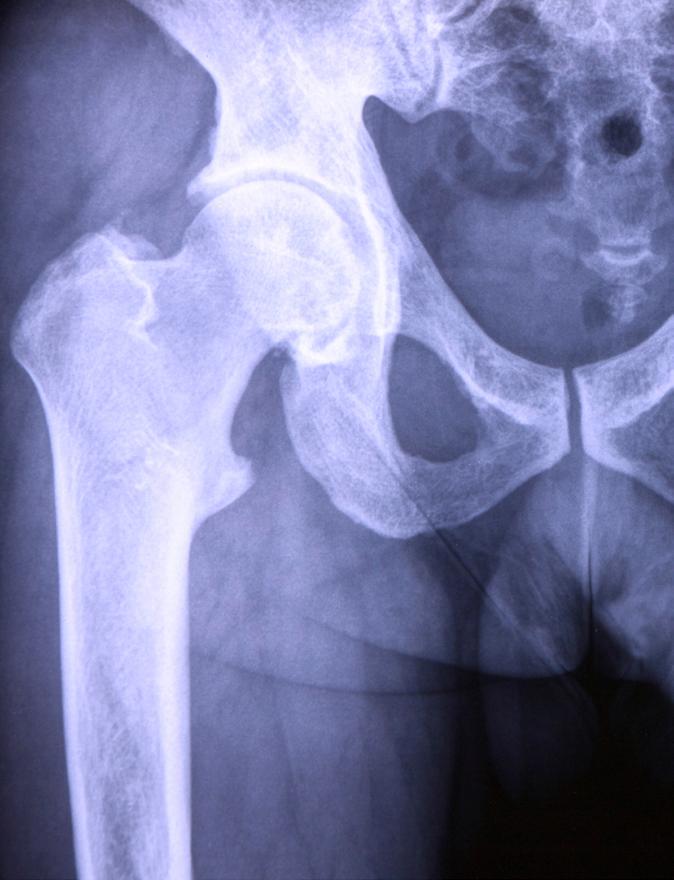

An external inquiry into issues with hip operations performed on children at Addenbrooke’s Hospital in Cambridge has been expanded to cover 800 patients.

The initial external review was carried out by an independent expert and considered a number of complex paediatric hip surgery cases performed by the Trust’s orthopaedic service over the past two and a half years. That review was completed in January and identified that the outcomes of treatment provided to nine children were below the standard expected. The Trust has now said that the review will be extended to a further 800 patients –both children and adults.

“The findings of the initial external review were extremely disturbing. Since then, not only have we been contacted by some of the families, but we’ve also heard heartbreaking stories from other families outside the scope of that initial review about their child’s treatment,” said Catherine Slattery, associate solicitor at Irwin Mitchell which is supporting a number of parents with concerns about orthopaedic operations. “That 800 cases will now be looked at is truly staggering,” she added.

The latest review will be led by barrister Andrew Kennedy. He will examine treatment provided to 700 patients who underwent planned operations. The review will

also scrutinise 100 adult and child patients who underwent emergency surgery.

“While the individual surgeon specialises in paediatric surgery, it is normal practice for all orthopaedic consultants to carry out emergency orthopaedic procedures on both adults and paediatric patients. Therefore, as part of this retrospective review, the expert clinical panel will also review an initial 100 adults and paediatric orthopaedic trauma cases to determine whether there are any concerns about the emergency treatment provided by this surgeon,” the Trust explained.